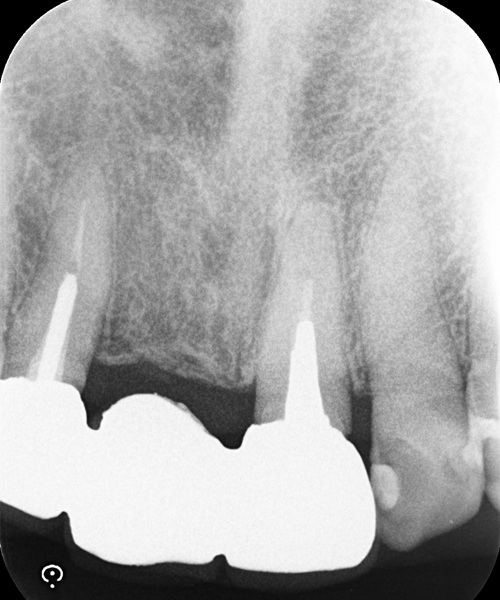

術前

術中

術後

| 治療名 | セラミックインレーによる虫歯の再治療症例 |

|---|---|

| 治療説明 |

過去に治療された銀歯が外れたとのことで来院されました。内部には古い接着剤の劣化と虫歯の再発が見られたため、しっかりと虫歯を除去し、セラミック製の詰め物(インレー)で再修復を行いました。 セラミックインレーは、天然歯に近い色調と自然な透明感を持っており、見た目が気になる部位にも適しています。 |

| 治療回数・期間 | 2回 |

| 副作用とリスク | ・保険診療の銀歯に比べて費用が高くなります。 ・治療直後は一時的に知覚過敏のような症状が出ることがありますが、ほとんどの場合は数日〜1週間程度で落ち着きます。 |

| 料金(税込) | 77,000円 |